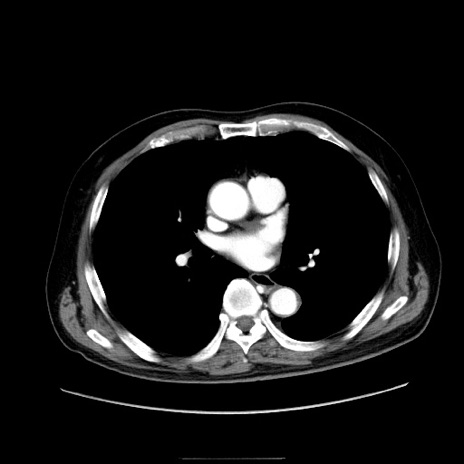

症例30(横断像)

冠状断像

【症例】80歳代男性

【現病歴】約6時間前から臍下部痛が出現。次第に腹部膨隆・背部痛も生じてきたため来院。背部痛の場所は変化しない。

【身体所見】意識清明、BT 36.3℃、BP  131/87mmHg、P 87bpm、SpO2 100%(RA)、臍周囲自発痛・圧痛あり、反跳痛なし、自発痛部位に一致して板状硬あり、腹部膨隆、腸雑音減弱、CVA tenderness両側陰性。